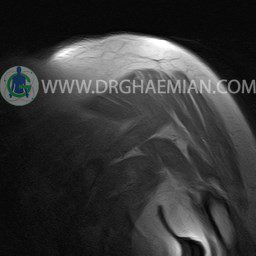

ام آر آی آتروفی عضلانی کتف بیمار

ام ار آی کتف یک روش تصویربرداری است که به وسیله آهنرباهای قدرتمند از قسمت کتف تصاویری ایجاد می کند. این نوع تصویربرداری از تشعشعات استفاده نمی کند. در این کیس آتروفی عضلانی کتف به همراه پارگی تاندون بالاخاری، بورسیت ساب دلتوئید و افیوژن مفصل دیده می شود.

– Complete tearing of supraspinatus tendon with grade 2 retraction and muscle atrophy

– AC joint hypertrophy with subacromial – subdeltoid bursitis

– Glenohumeral joint effusion

are seen.